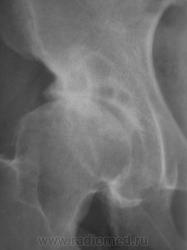

Сужение латерального отдела суставной щели, субхондральный склероз крыши суставной впадины, краевые остеофиты суставных поверхностей.Кистовидные просветления крыши вертлужной впадины и верхне-наружного квадранта головки бедренной кости.Головка бедра несколько уплощена. Пока-ДОА, 2-3 стадия.

Стопудова доа